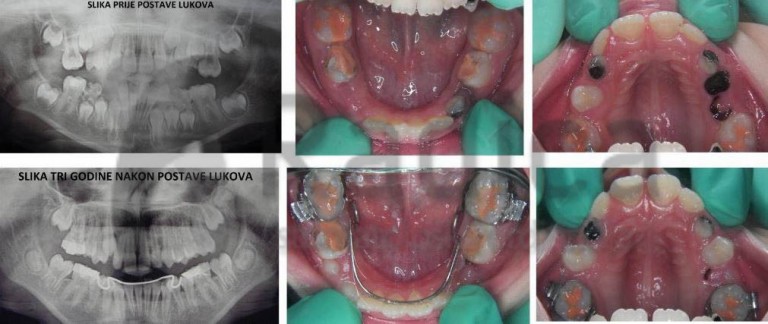

U slučaju da ipak dođe do preranog gubitka mliječnih zuba preporučuje se napraviti držače mjesta, transplatinalni i/ili lingvalni lukovi koji sprječavaju pomak „šestica“ i čuvaju mjesto za trajne nasljednike.

Nažalost, najveći broj ortodontskih pacijenata u Hrvatskoj upravo su oni koji su prerano izgubili mliječne i/ili trajne zube jer ih nisu prali niti odlazili stomatologu.